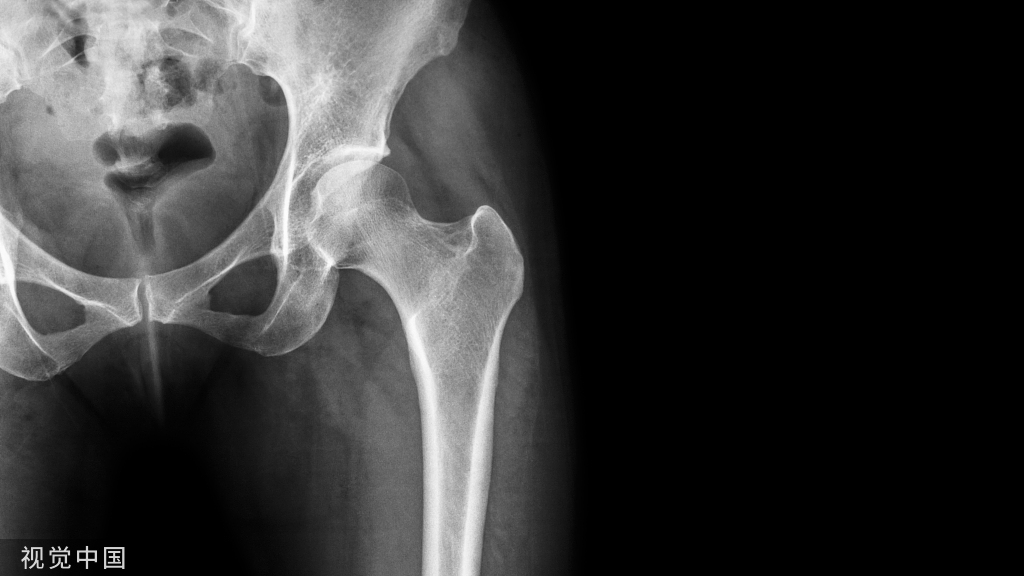

香港大学(港大)医学院于2022年5月19日公布了一项研究,提示感染新冠病毒可能诱发破骨细胞的炎症,致使患者在感染期和康复后期,出现严重的骨质流失。研究团队认为,这可能是一种被忽视的新冠并发症。

为了研究新冠病毒对骨组织代谢的影响,研究团队在叙利亚仓鼠模型鼻内注入新冠病毒,并收集它们受感染后的骨组织样本。通过三维微米级计算机断层成像技术,团队发现感染新冠病毒会引起长骨及椎骨等部位内的小梁骨结构,出现20%~50%不等的严重骨质流失。急性感染所引起的骨质流失,更会持续较长时间。